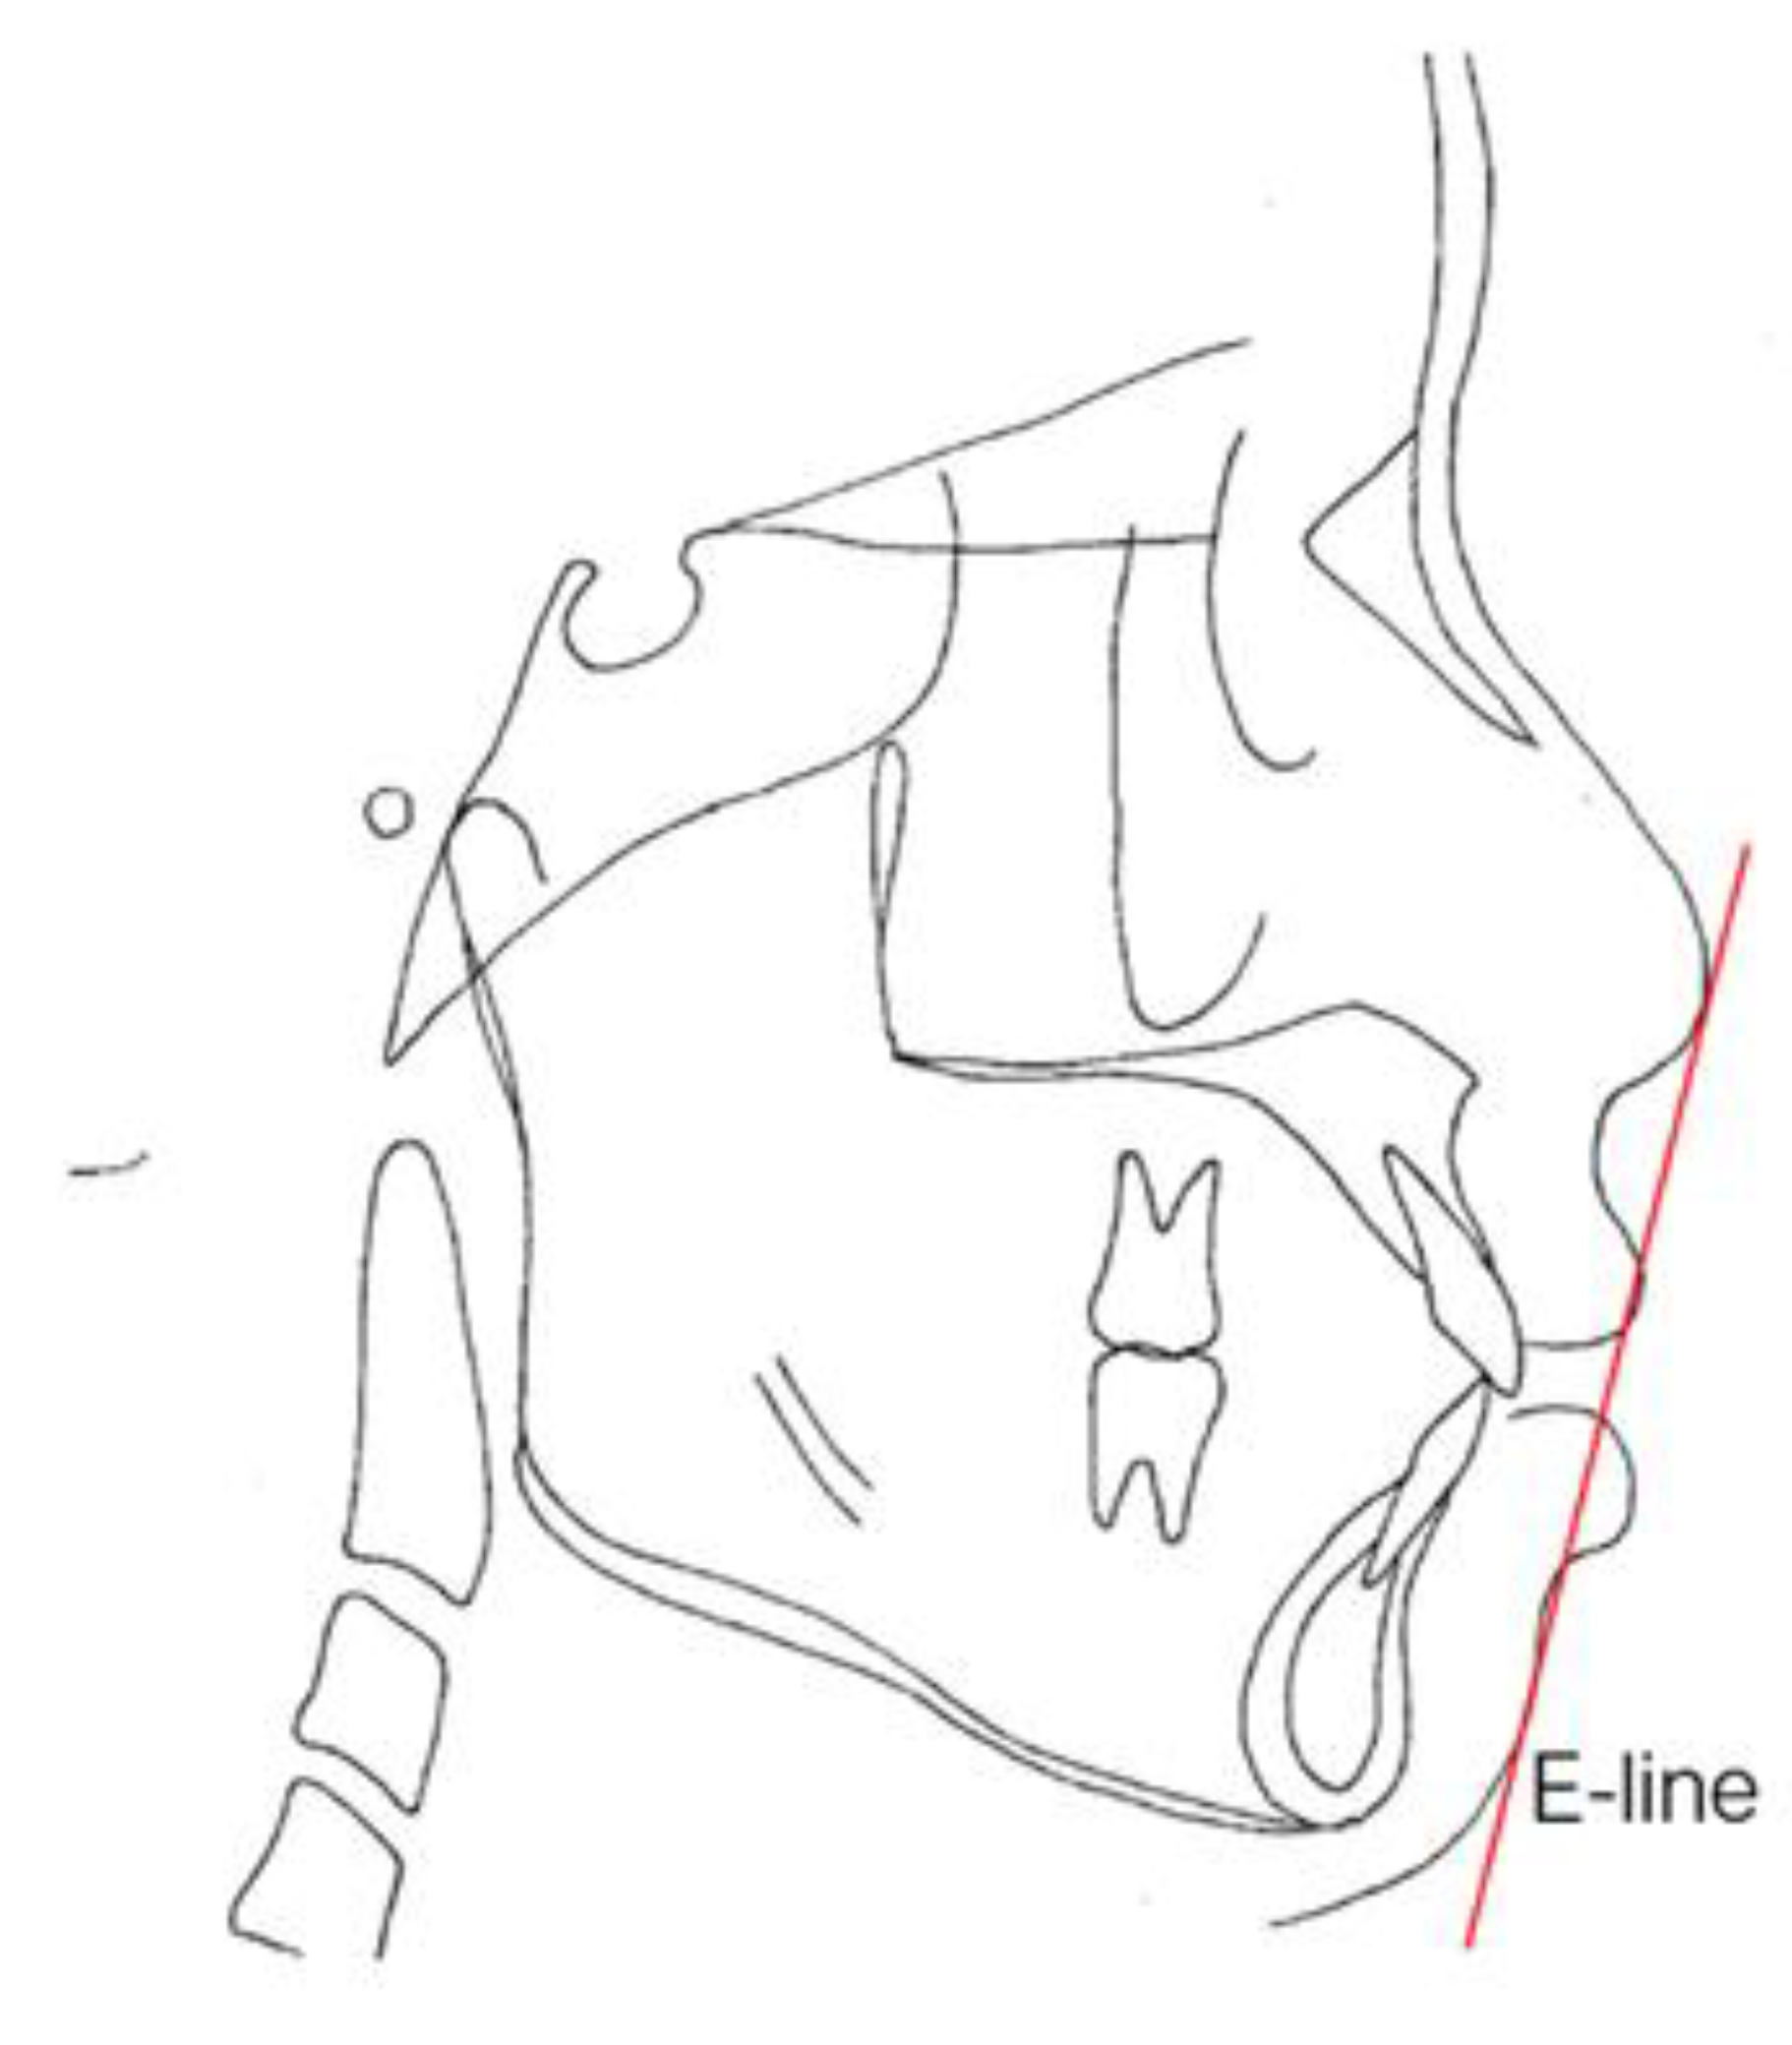

The Frankfort–mandibular plane angle (FMA) and sella-nasion (SN) to mandibular plane angle are often used to describe these three facial patterns in orthodontics (Figure 5 and Figure 6). FMAs between 27 and 34 are classified as average angles, FMAs less than 27 are classified as low angles, and FMAs larger than 34 are classified as high angles according to the data from the Taiwan Association of Orthodontists. Ricketts E line [42] (a reference line from the chin to the tip of the nose), Holdaway’s H line [43] (a line from the chin to the upper lip), Steiner’s S1 line [42] (a line from the chin to the midpoint bisecting the nasal nostril border line), Burstone’s B line [44] (a line from the chin to the subnasale), Sushner’s S2 line [45] (a line from the soft tissue nasion to soft tissue pogonion), and Merrifield’s profile line and Z angle (an angle formed by a chin-protrusive line intersecting the Frankfort horizontal plane) [37] were used to analyze the facial configurations.

E-lines and Z angles are often used for the evaluation of facial esthetics in our department of Chang Gung Memorial Hospital [37]. The lip protrusion is judged by relating it to the esthetic line (E-line). The E-line (Figure 7) is formed by joining the tip of the nose and soft tissue pogonion, which is the most protrusive point of the bony mandible. The upper lip should be tangent to the line; the lower lip should be tangent or slightly behind the E-line for Caucasians, but there is more variation from 0.2 to 4.3 mm between male and female Taiwanese. The Z angle is another angular measurement for the critical description of the esthetics of the lower face (Figure 8). This angle is formed by the Frankfort plane, and the profile line is formed by a line tangent to the soft tissue chin and to the more prominent lip. The Z angle range is typically 70–80 degrees.

Figure 7. Esthetic line (E-line). The line drawn from the tip of the nose to tip of the chin.